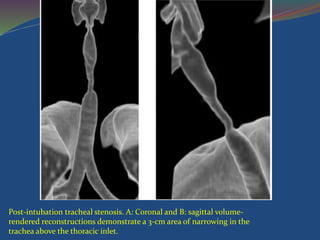

Post-intubation tracheal stenosis. A: Coronal and B: sagittal volume-

rendered reconstructions demonstrate a 3-cm area of narrowing in the

trachea above the thoracic inlet.